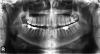

Первый приговорил к удалению все восьмерки, а также две верхних четверки чтобы было место для маневров. К тому же хирургом была приговорена к удалению семерка слева сверху (из за кариеса под десной). В итоге получается удалять 7 зубов =(

Мнение второго ортодонта более обнадеживающее: т.к. семерка слева сверху идет под удаление, то восьмерку можно не удалять, а вытянуть ее с помощью брекетов на место удаленной семерки; сверху справа под удаление пойдет либо четверка, либо пятерка (точнее скажут через неделю после составления плана лечения), а также восьмерка. Ну и восьмерки снизу можно удалять уже в процессе ортодонтического лечения.

Хочу спросить у специалистов - насколько адекватен диагноз второго врача? Стоит ли вытягивать брекетами восьмерку, или же лучше удалять?